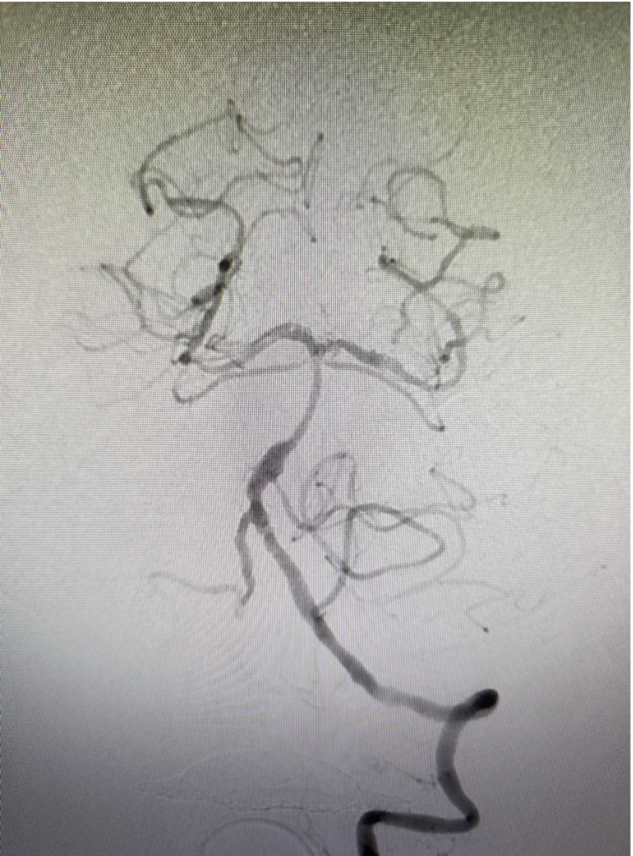

造影显示基底动脉远端闭塞,建立血管内治疗通路:Locaste长鞘同轴带领Skathi远端通路导管到位。

微导丝超选至右侧大脑后动脉,微导管通过狭窄段困难。考虑原位狭窄,行球囊扩张。

球扩后狭窄改善后不能维持,沿微导丝微导管通过狭窄段至右侧大脑后动脉,释放Enterprise2支架一枚。

狭窄改善明显,前向血流维持良好,mTICI分级3级